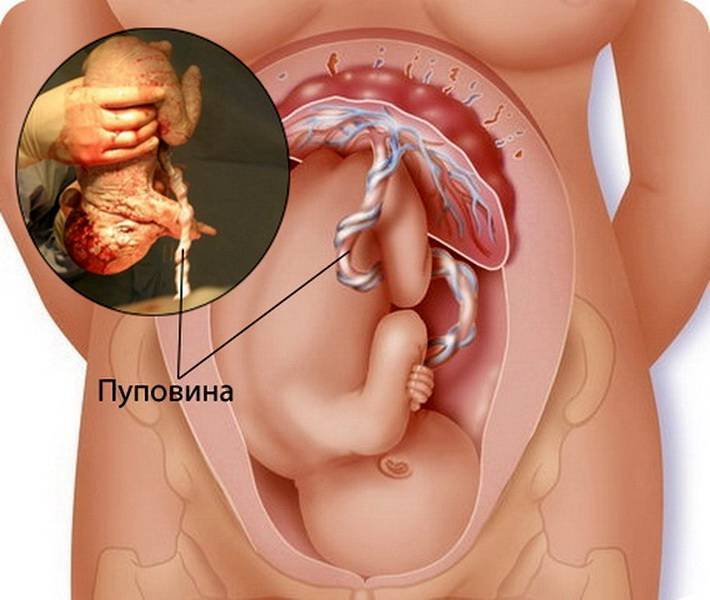

Моменты волшебства: Рождение ребенка в животе мамы

Раздел: Фотозарисовки